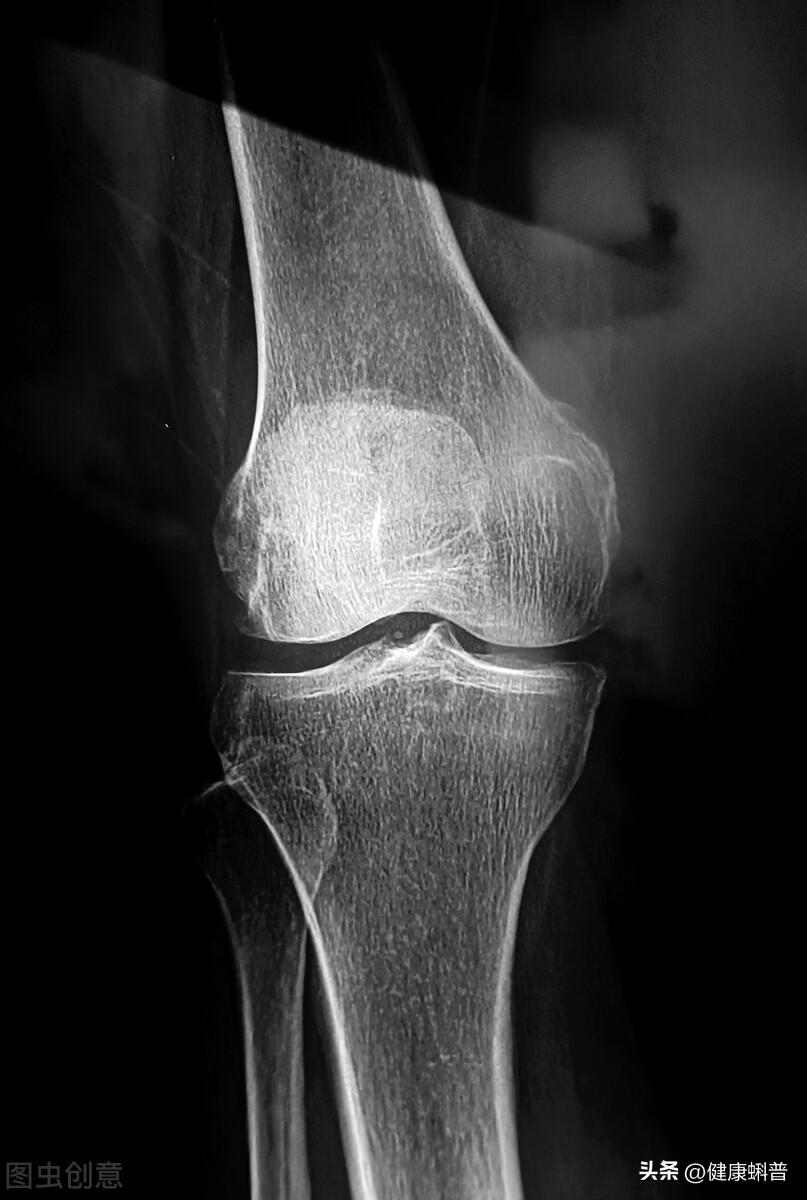

骨質(zhì)增生是人體骨骼的一種自然退變的衰老現(xiàn)象,是正常的生理現(xiàn)象,也是人體的一種自我保護機制。骨質(zhì)增生可通過影像學(xué)檢查發(fā)現(xiàn)。X線片檢查,45~65歲的中老年人約20%有骨質(zhì)增生的表現(xiàn),65歲以上的老年人約80%出現(xiàn)骨質(zhì)增生。

骨質(zhì)增生是一種退行性病變,是自然現(xiàn)象,常見于頸椎、腰椎、膝關(guān)節(jié)和腳后跟等部位。這些部位的關(guān)節(jié)常年受到擠壓、牽拉造成損傷。再有就是當(dāng)人體老化時,關(guān)節(jié)穩(wěn)定性變差,骨質(zhì)增生后以增加穩(wěn)定性。

以膝關(guān)節(jié)骨刺為例。骨刺長在膝關(guān)節(jié)脛骨平臺,緊挨著軟骨和半月板。通過針刀把“骨刺”剔除,很容易造成誤傷。而且更重要的是,即使剔除了,也不能杜絕不再長,不能“斷根”。這也是大連張老太太手術(shù)失敗的原因。